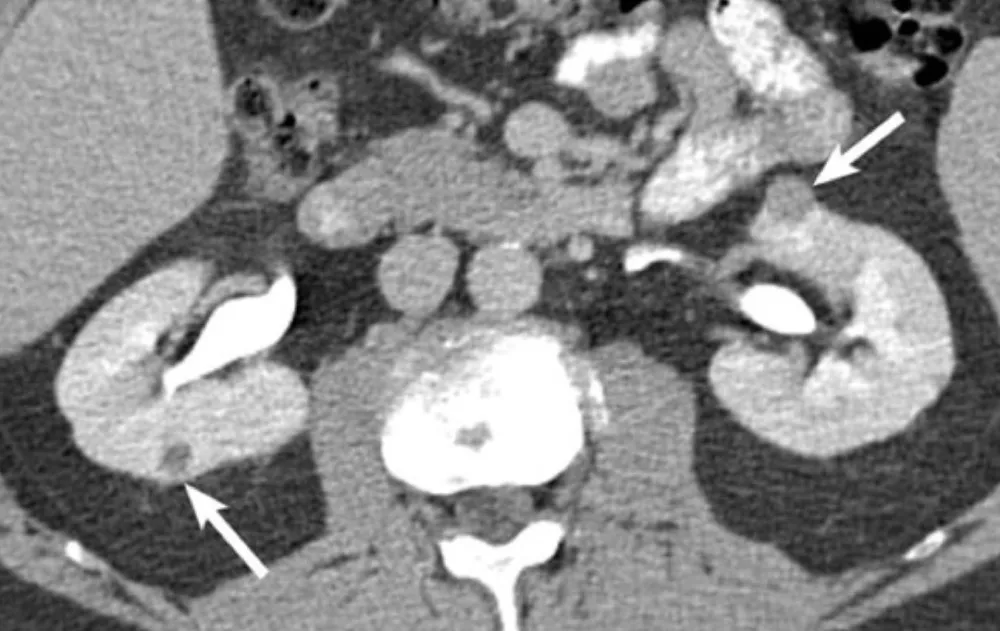

Hematuria e perda rápida da função renal em pacientes com câncer devem levantar suspeita de trombose da veia renal, mesmo sem contraste. Imagens não contrastadas e Doppler podem ser ferramentas-chave nesse contexto.

Valkercyo Feitosa

2 anos atrás